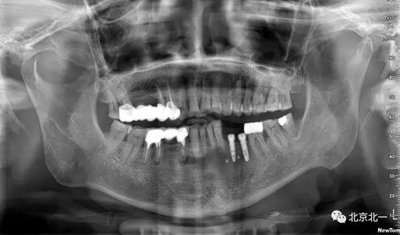

手術(shù)后半年觀察, 成骨良好。